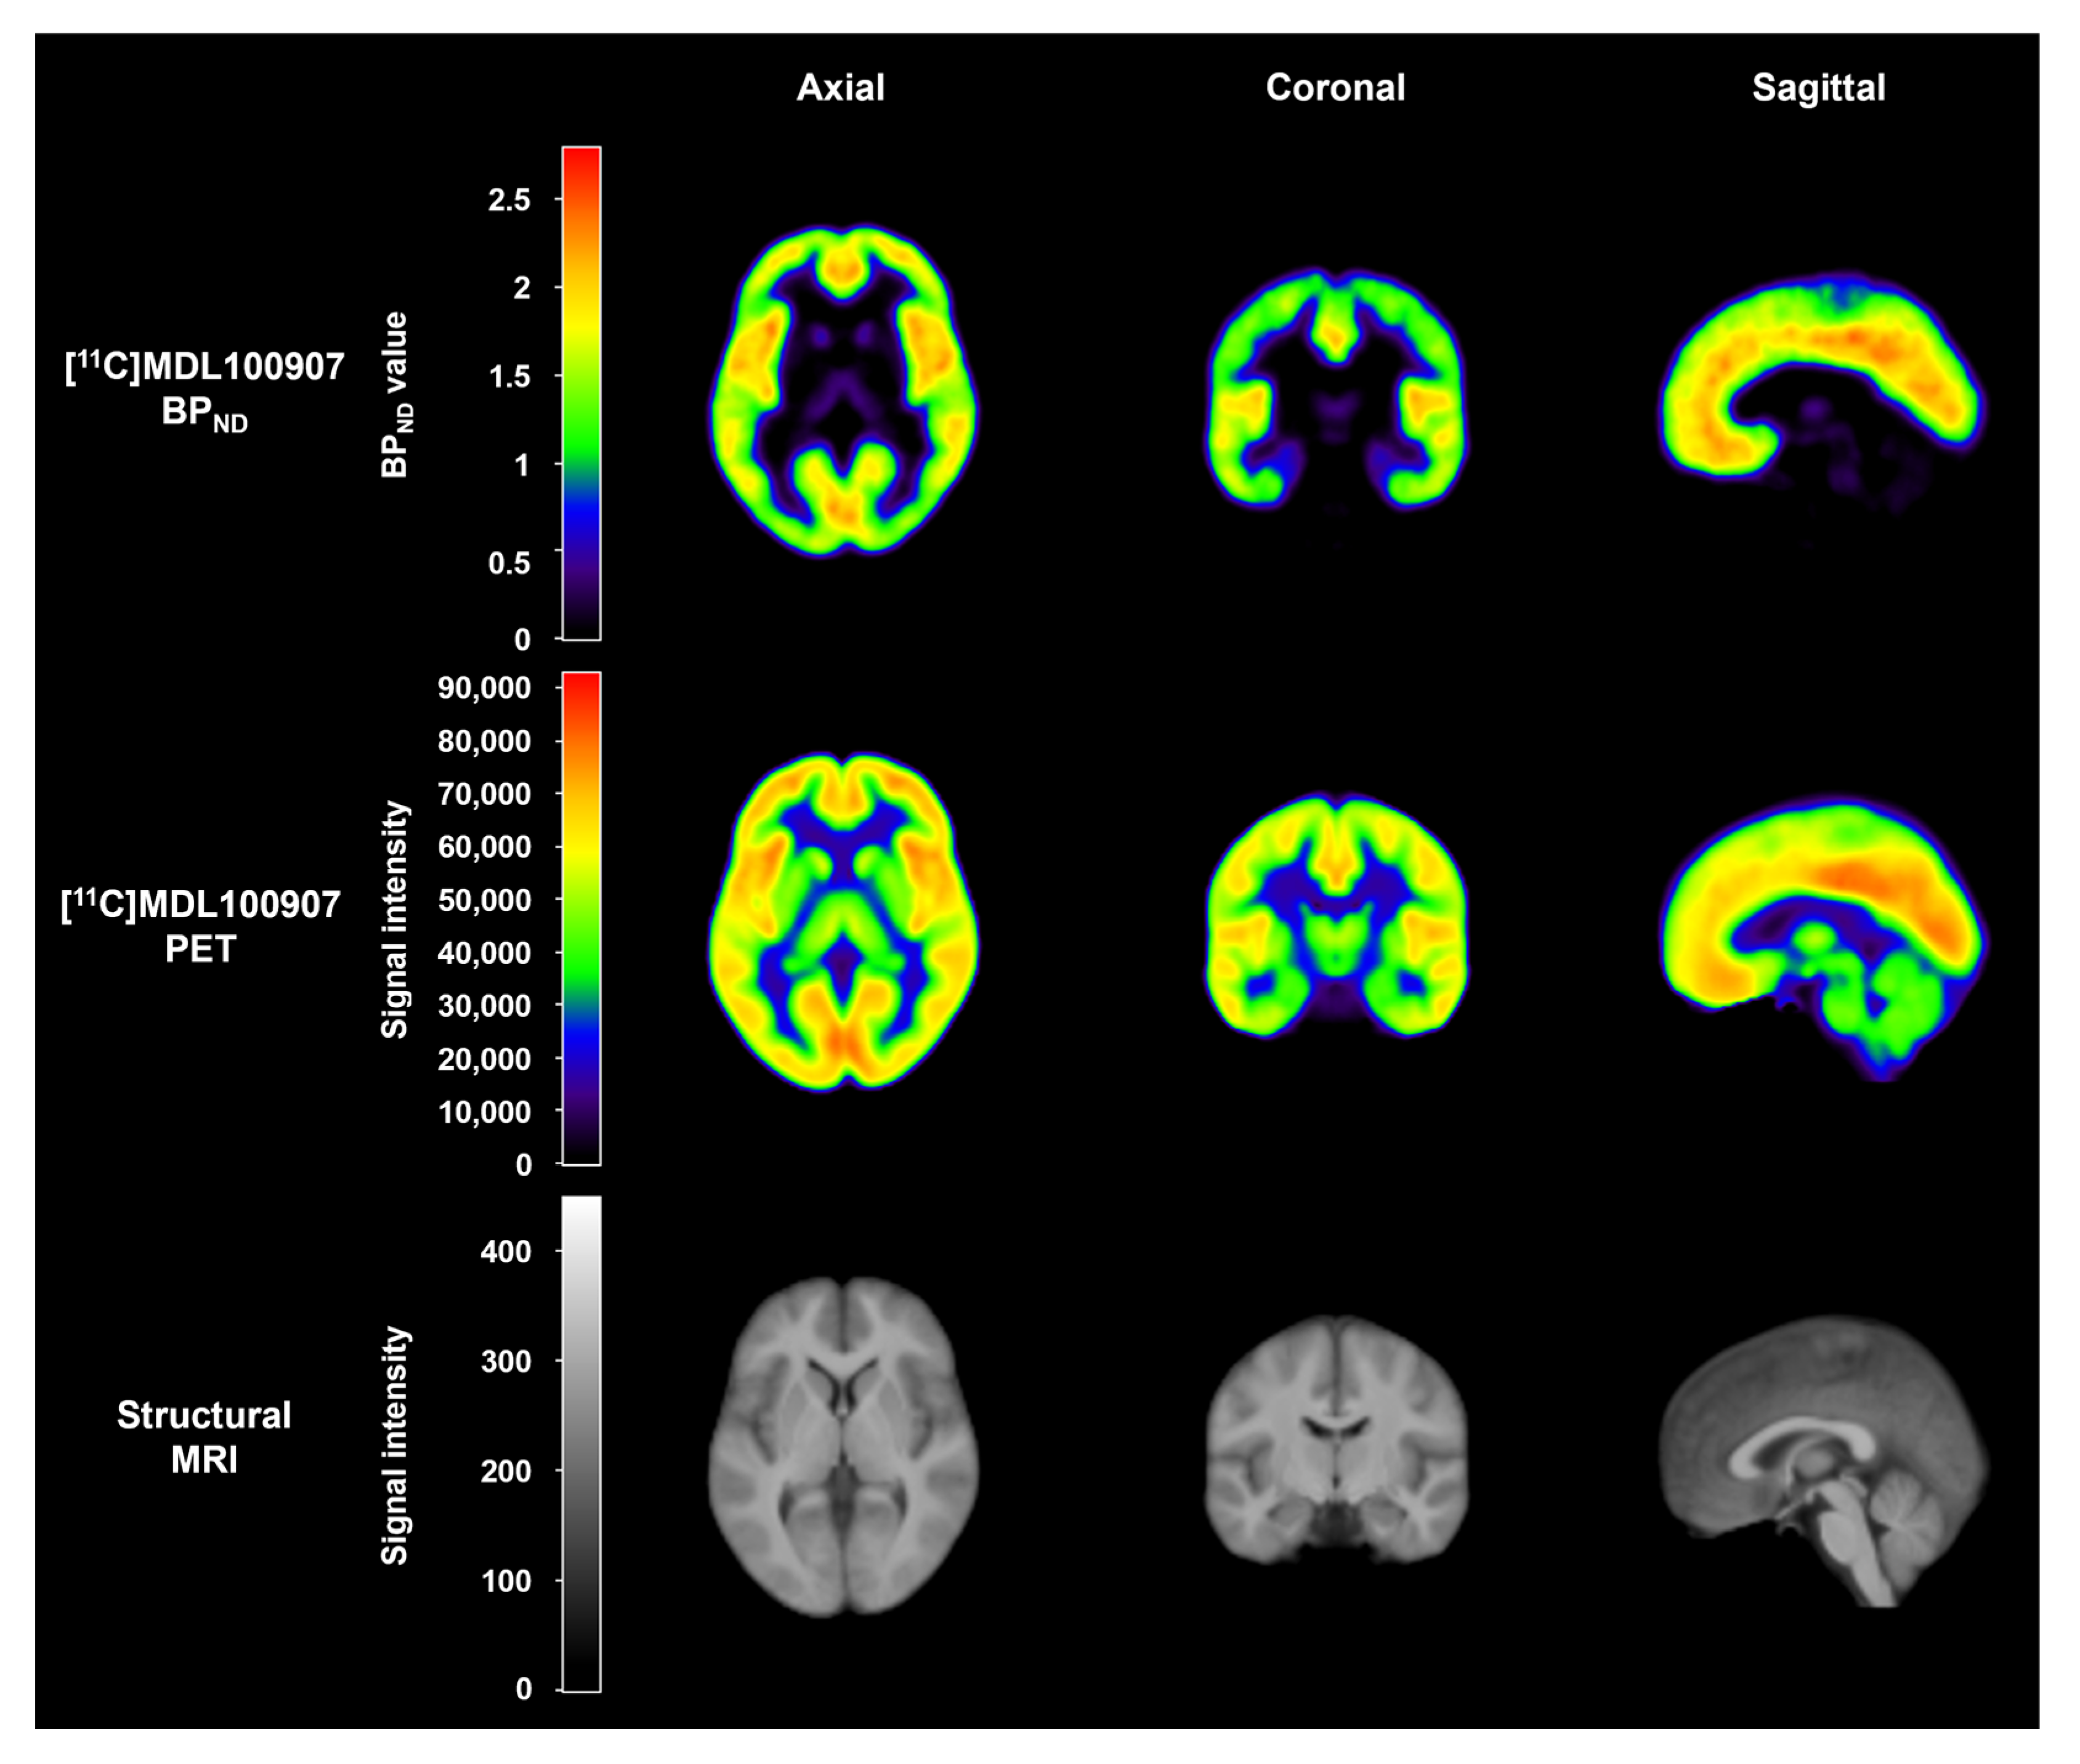

4.3. Image Acquisition

- Talbot, P.S.; Slifstein, M.; Hwang, D.-R.; Huang, Y.; Scher, E.; Abi-Dargham, A.; Laruelle, M. Extended Characterisation of the Serotonin 2A (5-HT2A) Receptor-Selective PET Radiotracer 11C-MDL100907 in Humans: Quantitative Analysis, Test-Retest Reproducibility, and Vulnerability to Endogenous 5-HT Tone. Neuroimage 2012, 59, 271–285. [Google Scholar] [CrossRef] [PubMed]

- Meyer, P.T.; Bhagwagar, Z.; Cowen, P.J.; Cunningham, V.J.; Grasby, P.M.; Hinz, R. Simplified Quantification of 5-HT2A Receptors in the Human Brain with [11C]MDL 100,907 PET and Non-Invasive Kinetic Analyses. Neuroimage 2010, 50, 984–993. [Google Scholar] [CrossRef]

- Hinz, R.; Bhagwagar, Z.; Cowen, P.J.; Cunningham, V.J.; Grasby, P.M. Validation of a Tracer Kinetic Model for the Quantification of 5-HT(2A) Receptors in Human Brain with [(11)C]MDL 100,907. J. Cereb. Blood Flow. Metab. 2007, 27, 161–172. [Google Scholar] [CrossRef]